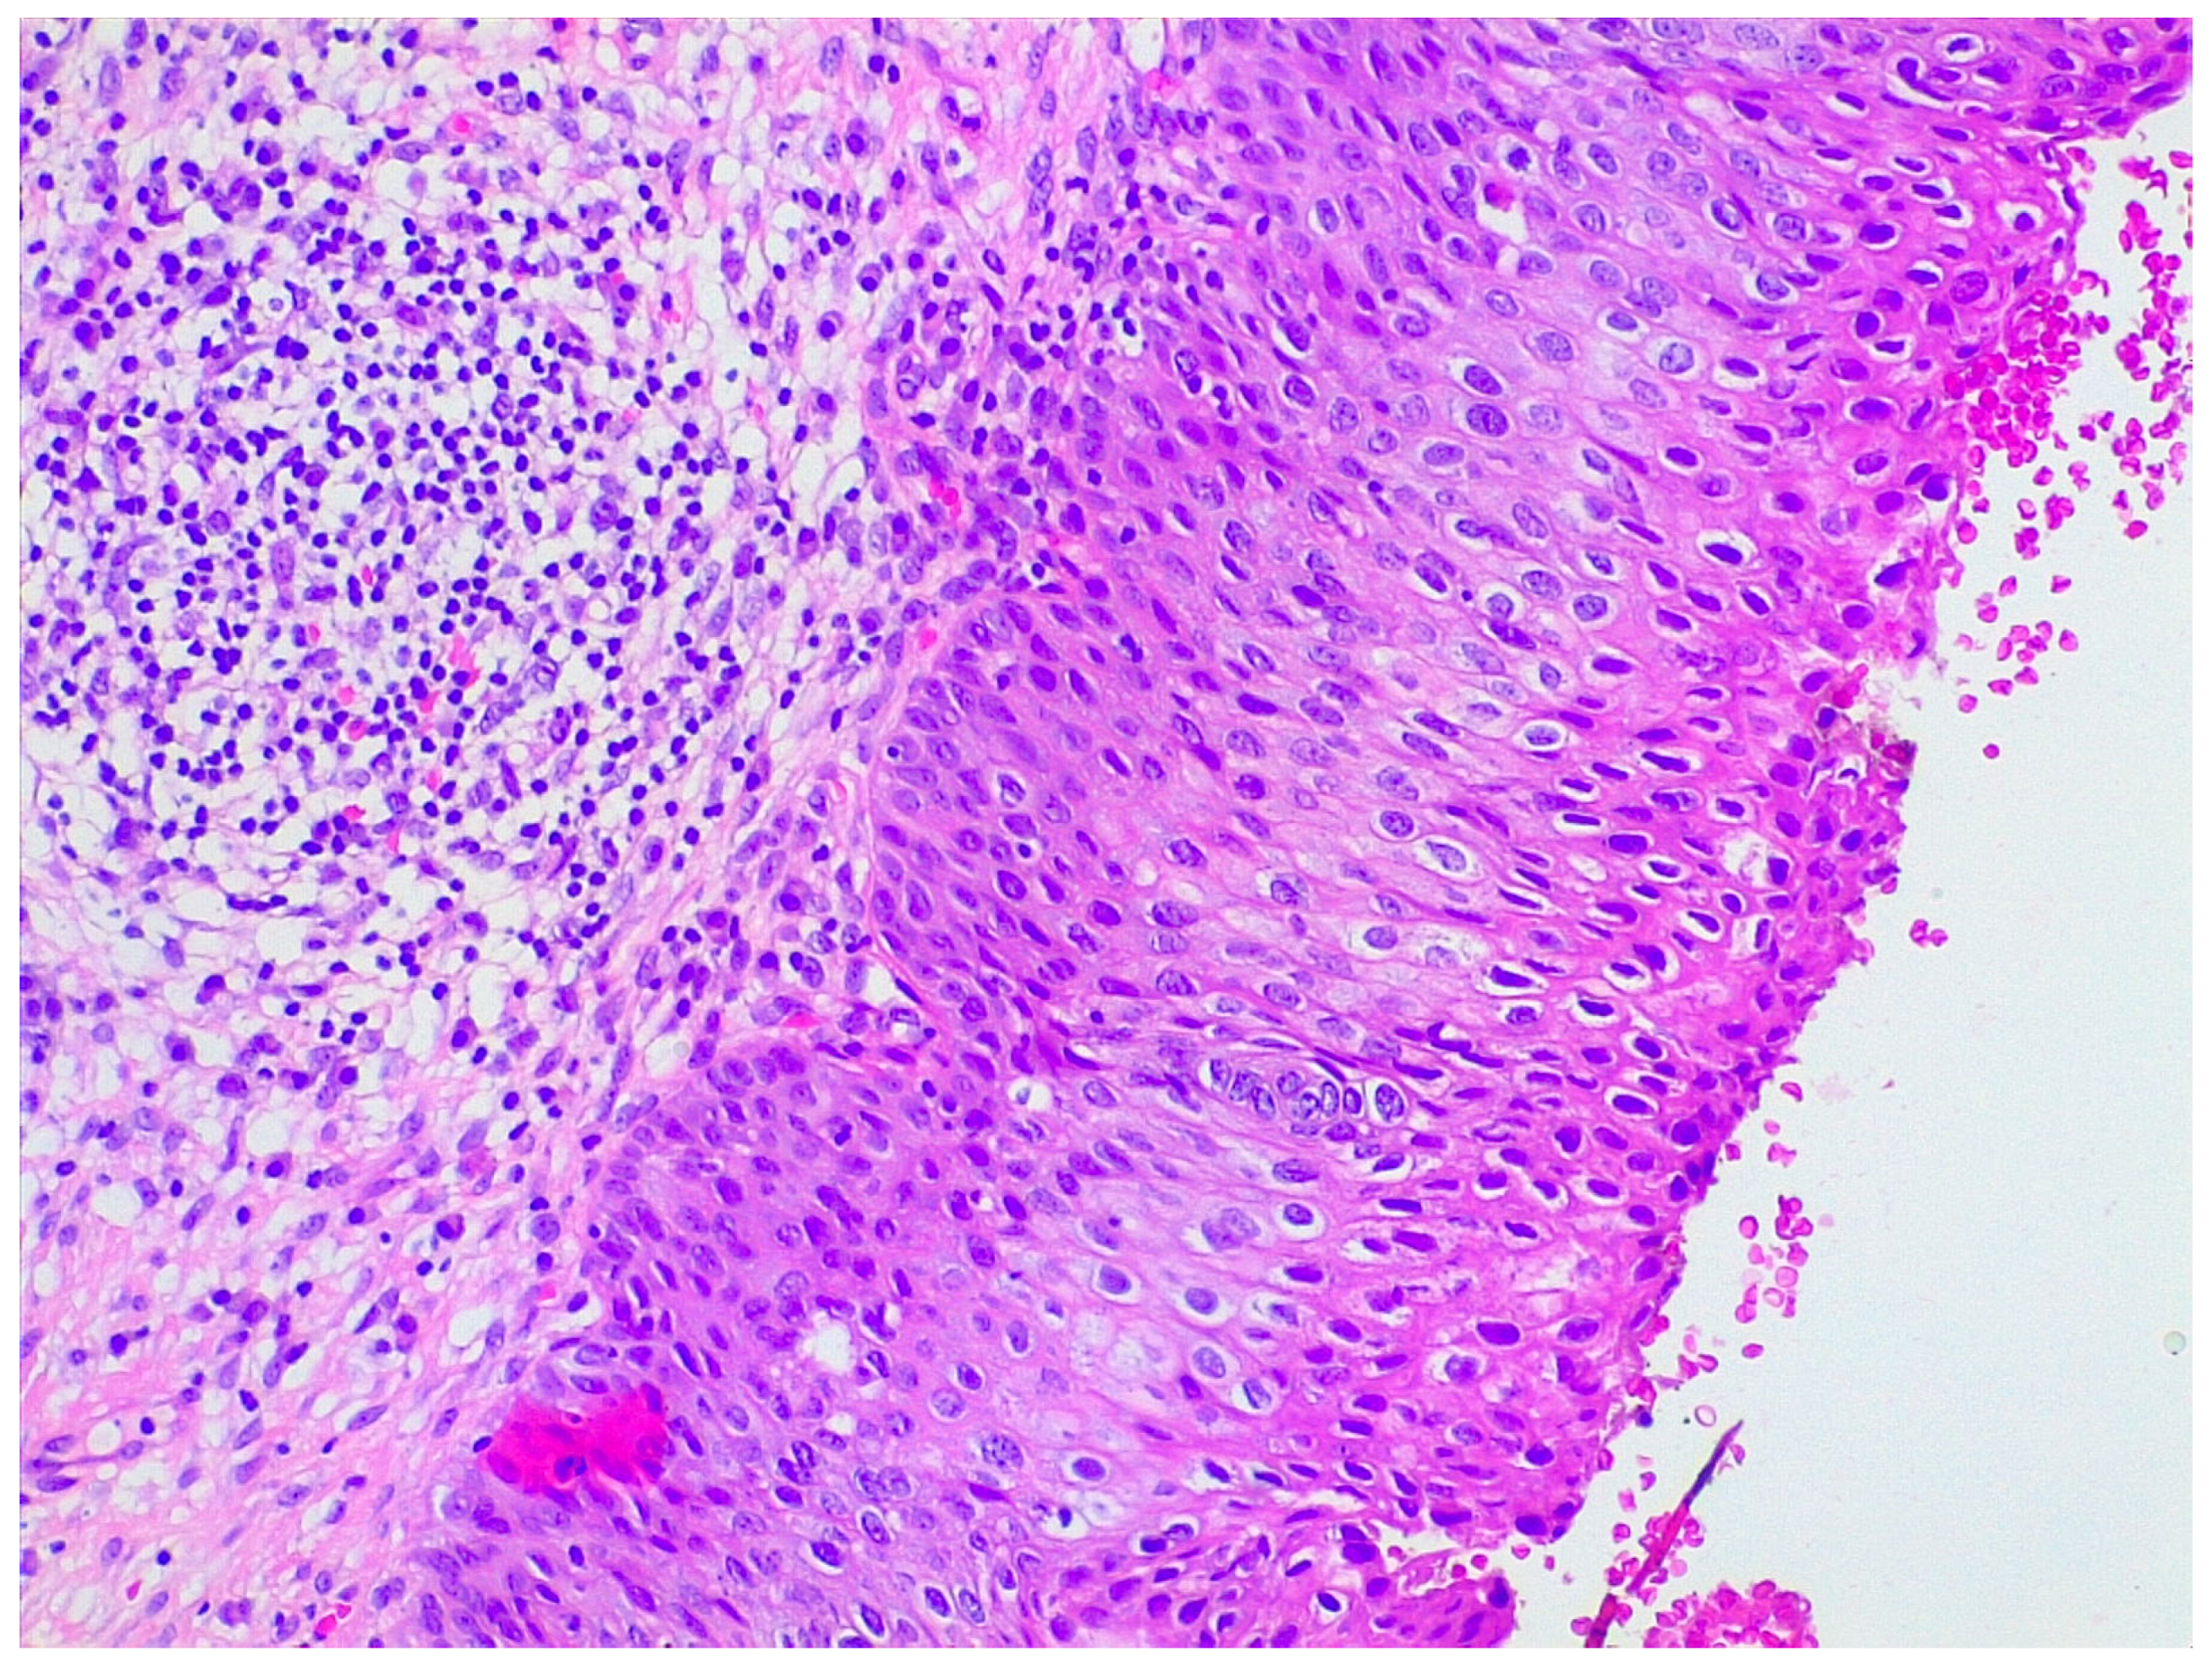

4.1. Neurotrophin Expression in Cervical Dysplastic and Neoplastic Lesions